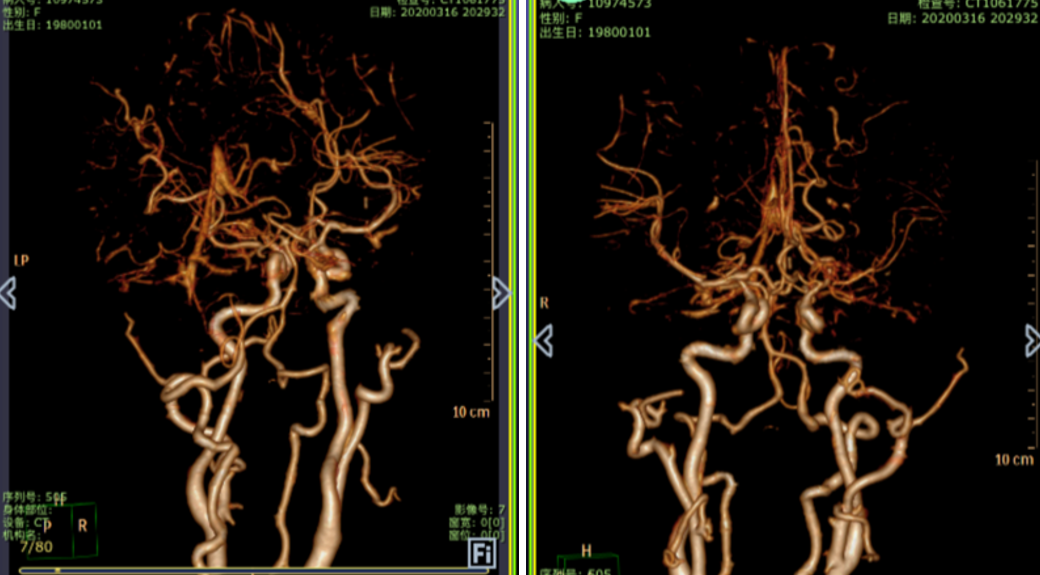

烟雾病

脉络膜前动脉假性动脉瘤

有观点认为此类动脉瘤可以保守治疗,因为较小的脑室旁动脉瘤可能自发消退,但同样存在保守治疗的病例预后不佳[1-4]。深部动脉瘤通过血管内介入治疗往往能取得较好的疗效,治疗能否成功关键取决于载瘤动脉直径[5]。血管内栓塞通常是烟雾病患者脑室旁动脉瘤的首选方案,因为可以避免开颅手术对脑实质的损伤及相关的缺血事件发生[1]。在一项病例系列研究[6]中,血管内栓塞成功治疗了7例(88%)烟雾病伴脑室旁动脉瘤且无围术期并发症,其中6名患者在出院时完全康复(75%)。然而,烟雾病患者载瘤动脉往往十分迂曲,且动脉瘤容易破裂[5]因此血管内治疗往往充满挑战。显微手术夹闭是动脉瘤的传统治疗方法,但在治疗深部动脉瘤时,术中破裂的风险可能更高。微创手术如小骨窗和神经内镜已用于治疗颅内深部病变,并取得了不同程度的成功。

在本例病例中,针对脑室内动脉瘤,我们首选血管内治疗栓塞脑室旁动脉瘤,因为血管过于迂曲尝试失败。术后出现脑室内出血,于是启动备选方案,急诊在磁共振导航下通过endoport辅助进行动脉瘤切除,同时部分清除脑室内血肿并放置脑室外引流,降低远期脑脑积水的风险。随着神经内镜的普及,深部的脑血管病变的治疗方案有了更多的选择,而充分的术前评估与周全的手术方案规划是手术安全与成功的基石。